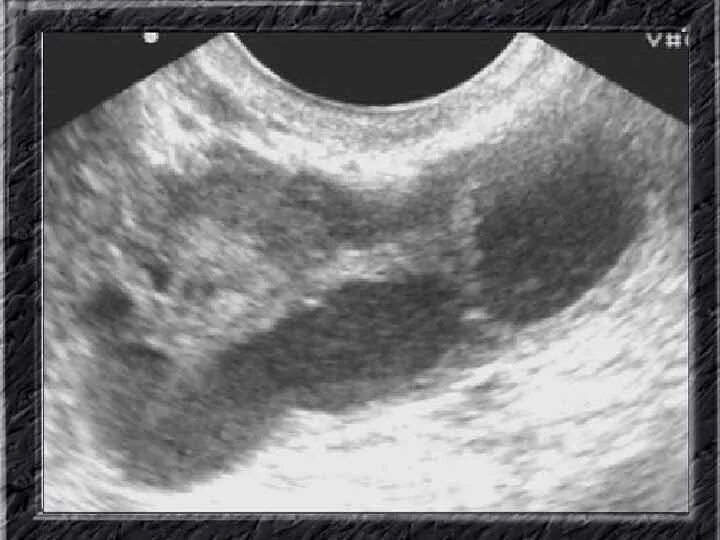

Сальпингит и оофорит что это